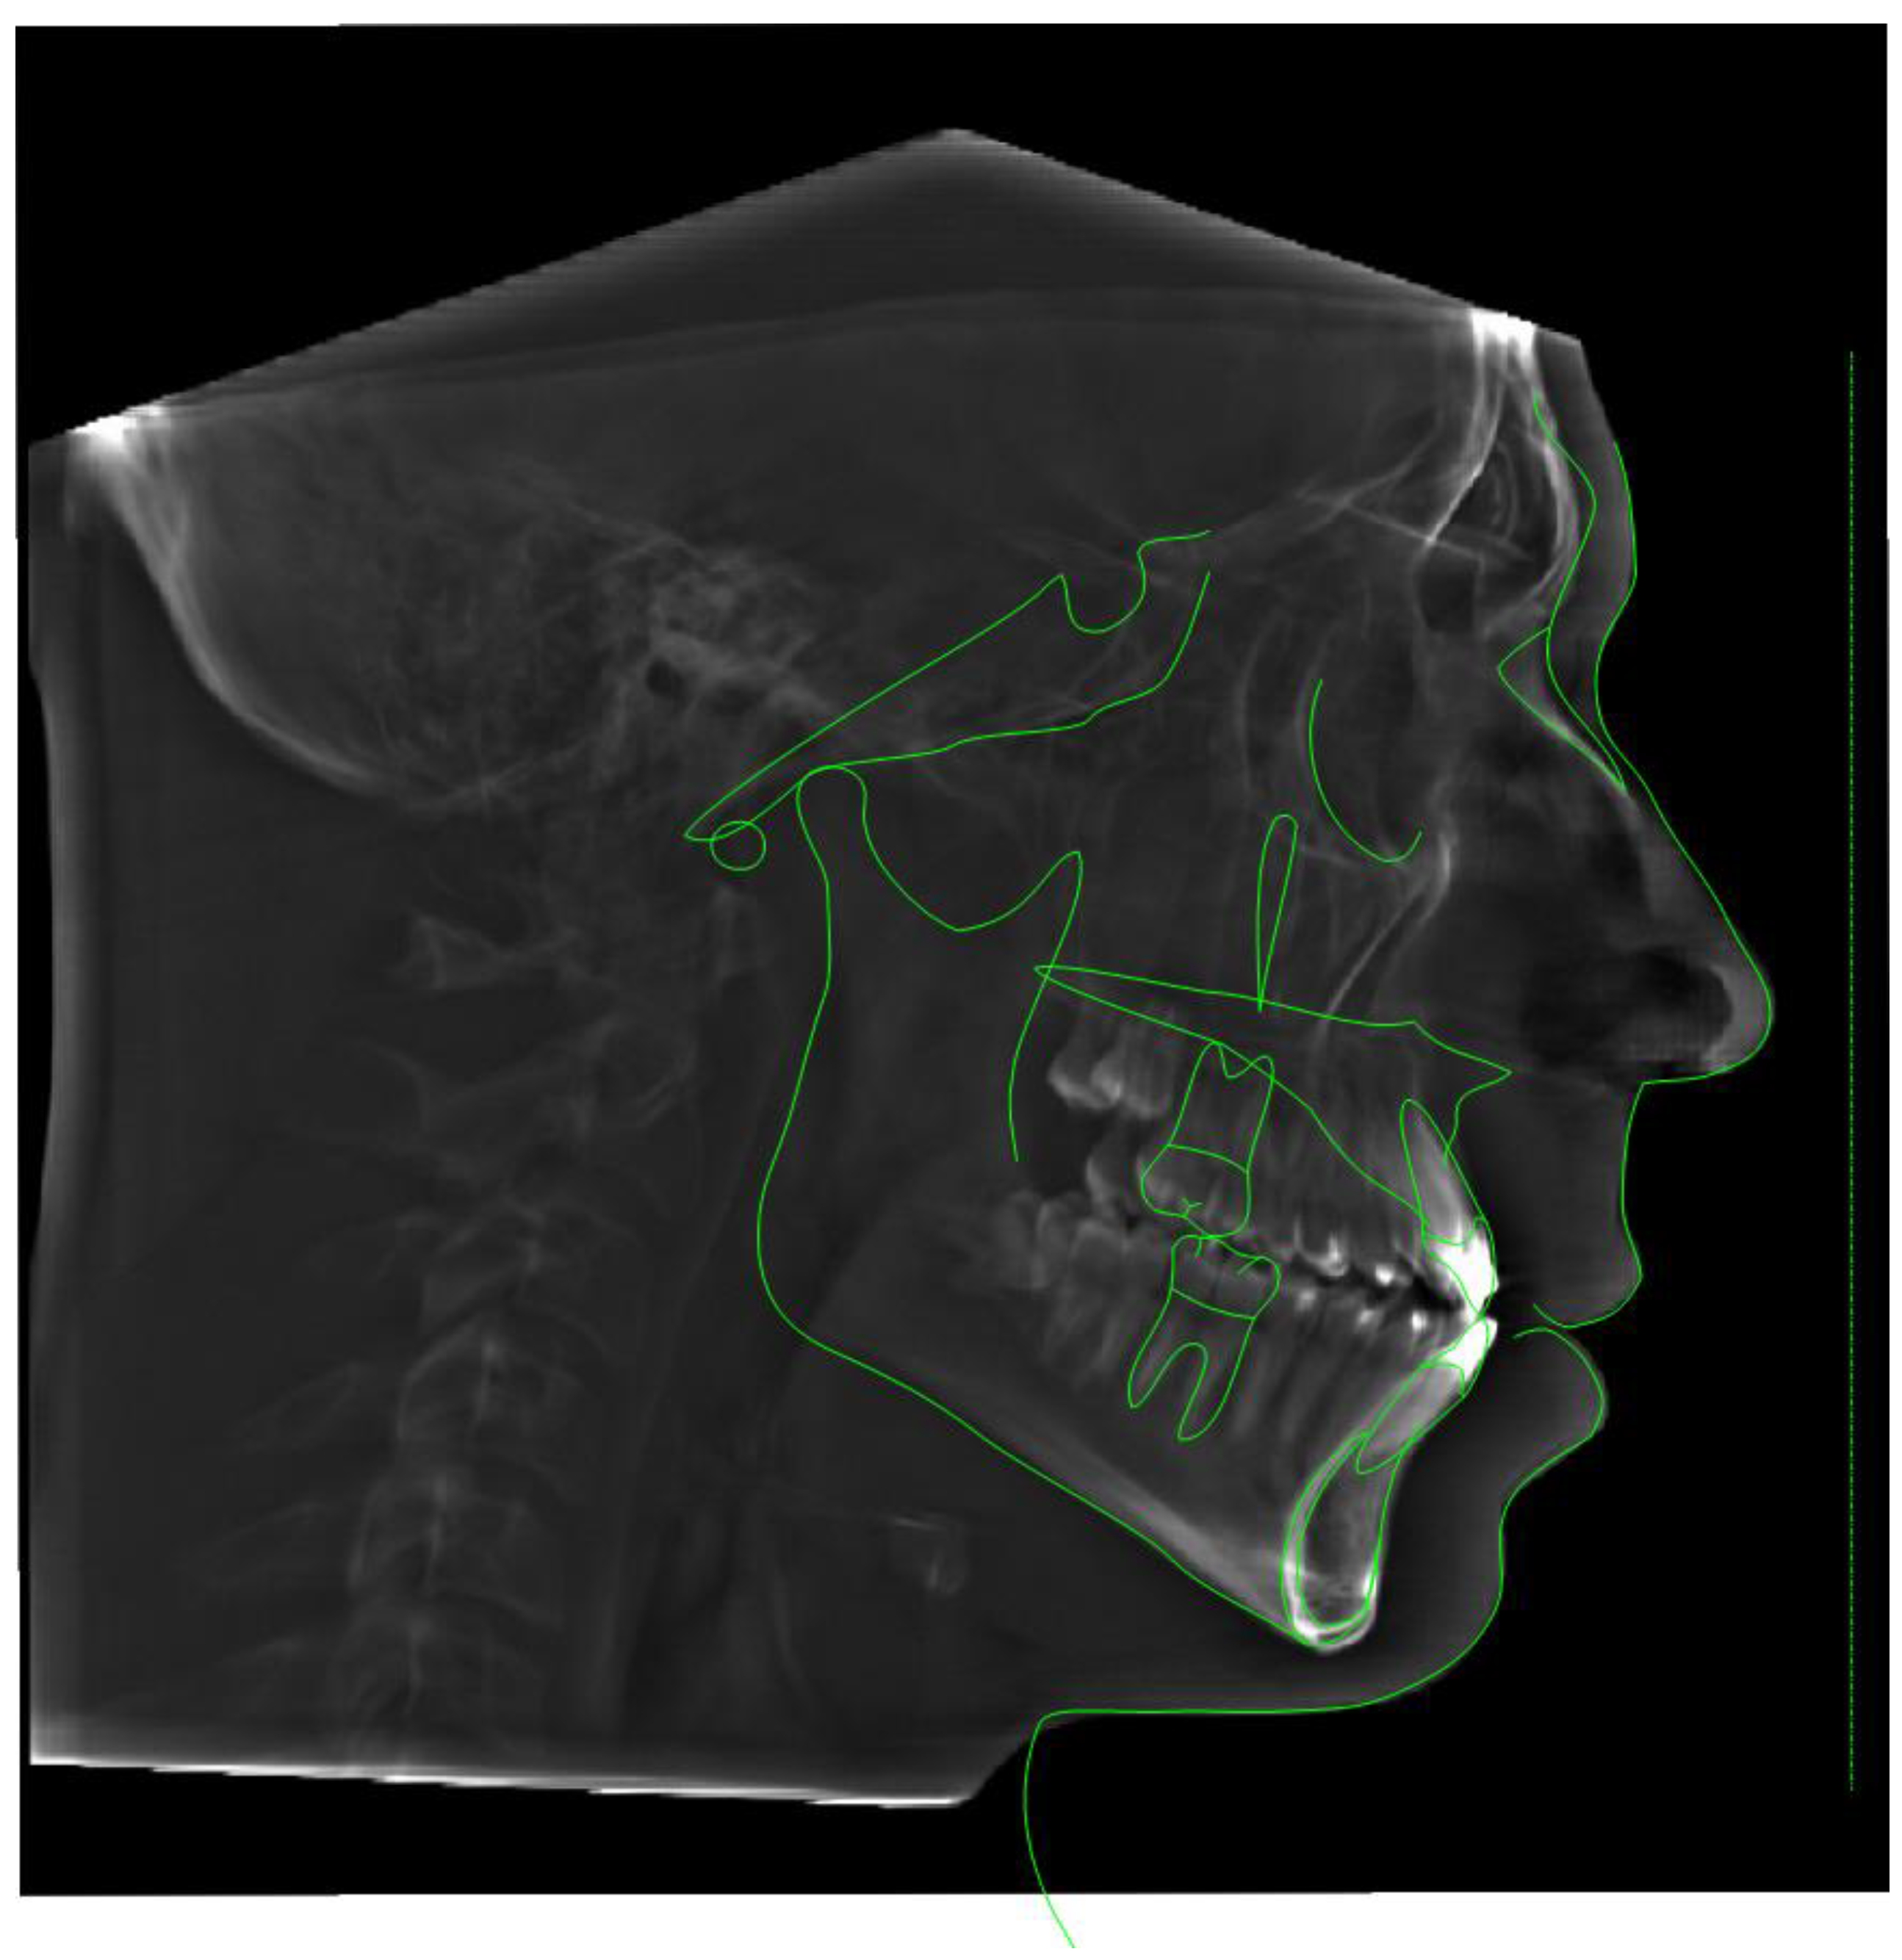

Initial records included the CBCT of the head and neck. The full face CBCT was taken with a Planmeca Viso G7 (Planmeca, Helsinki, Finland) at 30 Sv-6, 100 kV, and a 600 Voxel Ultra Low Dose (ULD) setting slice with a 19’’x19’’ sensor area with the patient in an upright position with natural head posture and occipital head support. A pre-treatment lateral cephalometric radiograph was rendered from the CBCT, traced, and evaluated via Roth–Jarabak analysis (Table 1, Fig. 1.).

Figure 1. Lateral cephalometric tracing before treatment indicating Skeletal Class I according to the ANB angle. Brachyfacial facial pattern with increased buccal inclination of maxillary and mandibular incisors and anterior crossbite.